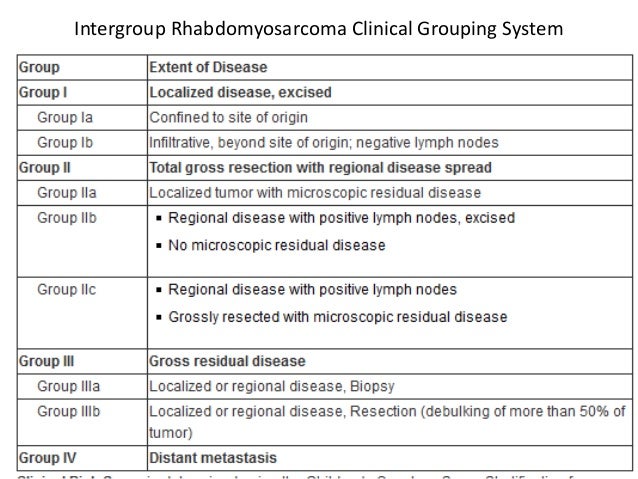

Rhabdomyosarcoma

rhabdomyosarcoma intergroup grouping